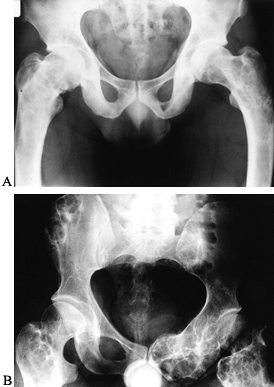

stage 3 disease. The radiographic appearance of an ABC is quite

distinctive and almost diagnostic (Fig. 127.8A).

The characteristic features include a subperiosteal lytic expansile

lesion inflating and thinning the cortex. In the early stages,

periosteal reaction is scarce, giving the appearance of a malignant

tumor. The lesion typically involves the metaphysis, and occasionally

the epiphysis, and it may even cross the physis. Because the periosteal

response may extend along the shaft of the bone beyond the lesion, it

may have the appearance of a finger in a balloon. Most often the lesion

is eccentric, but it can be central. In the

spine,

the lesion typically involves the posterior elements but may expand to

involve the vertebral body as well as adjacent vertebrae. CT and MRI

are useful imaging modalities, especially in the axial skeleton. They

are particularly helpful in confirming the diagnosis by demonstrating

the characteristic fluid levels within the cyst (Fig. 127.8B).

It should be stressed, however, that the presence of these fluid–fluid

levels is not pathognomonic for ABC. Other lesions, including GCT,

unicameral bone cyst with fracture, and osteosarcoma, may have this

finding.

![]() |

|

Figure 127.8. A:

AP radiograph of an aneurysmal bone cyst (ABC) shows an expanded radiolucent lesion in the metaphysis of the right distal tibia. The periosteum is intact and well marginated. There are some internal septations within the lesion. B: An MRI of this lesion shows the classic fluid–fluid levels. This was biopsied and proved to be an ABC. |